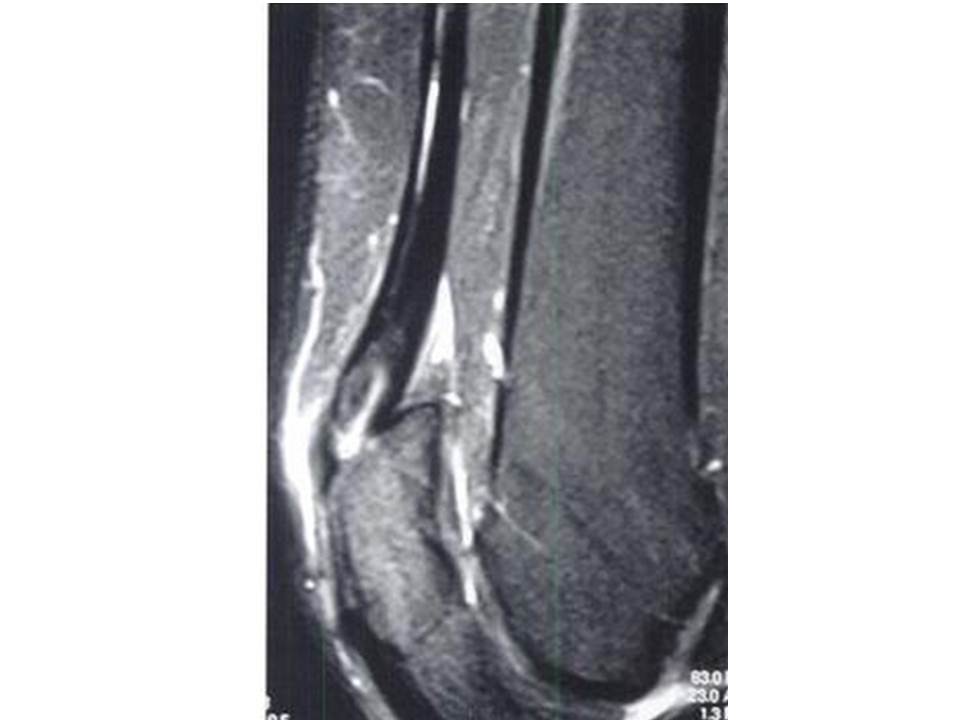

Quadriceps Tendonitis Mri . To confirm the diagnosis, your. We examined this layered configuration on mr images to determine if it is relevant in the evaluation of the traumatized quadriceps tendon. For example, computed tomography (ct) or magnetic resonance imaging (mri) of the knee can exclude any acute bony injuries, meniscus tears, or ligament injuries. The quadriceps tendon is a multilayered and laminated structure, as shown by anatomical specimens and mri scans. While this part of the examination can be painful, it is important to identify a quadriceps tendon tear. Diagnosis is made clinically with.

While this part of the examination can be painful, it is important to identify a quadriceps tendon tear. The quadriceps tendon is a multilayered and laminated structure, as shown by anatomical specimens and mri scans. To confirm the diagnosis, your. Diagnosis is made clinically with. For example, computed tomography (ct) or magnetic resonance imaging (mri) of the knee can exclude any acute bony injuries, meniscus tears, or ligament injuries. We examined this layered configuration on mr images to determine if it is relevant in the evaluation of the traumatized quadriceps tendon.